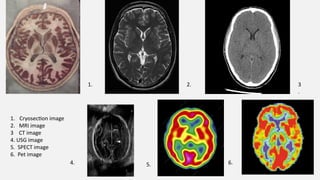

1. Cryosection image

2. MRI image

3 CT image

4. USG image

5. SPECT image

6. Pet image

1. 2. 3

5. 6.

4.